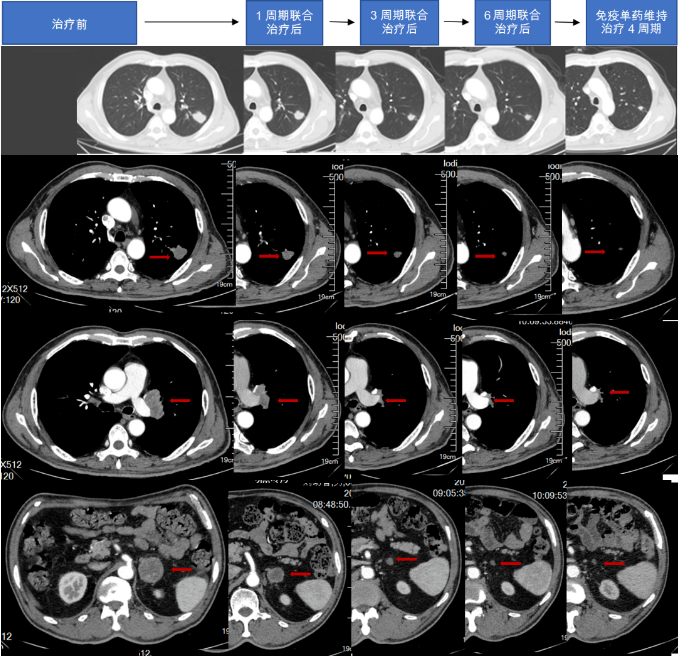

综合治疗1周期影像学报告(2022-09-07):结合病史,1、肺Ca复查,左肺上叶占位并左肺门多发肿大淋巴结,较前(2022-08-08)减小;双侧肾上腺占位,较前减小;腹膜后淋巴结转移,较前略减小;左侧颈部淋巴结转移,部分较前减小,请结合临床并复查。2、双肺肺气肿,多发肺大泡;双肺下叶少许炎症;左肺下叶钙化灶3、主动脉壁及冠状动脉壁钙化斑块。

综合治疗3周期影像学报告(2022-10-23):结合病史,肺Ca复查,左肺上叶占位,较前(2022.09.07)减小,左侧肺门淋巴结较前缩小;左侧肾上腺占位,较前减小;腹膜后小淋巴结,较前变化不著;左侧颈部淋巴结转移,较前减小。2、双肺肺气肿,多发肺大泡;双肺下叶少许炎症;左肺下叶钙化灶3、主动脉壁及冠状动脉壁钙化斑块。

综合治疗6周期影像学报告(2023-02-02):结合病史,肺Ca复查,左肺上叶占位,较前(2022.10.23)变化不著;左侧肺门淋巴结较前略缩小;左侧肾上腺占位,较前似略有减小;腹膜后小淋巴结,较前变化不著;左侧颈部淋巴结转移,较前减小2、双肺肺气肿,多发肺大泡;双肺下叶少许炎症;左肺下叶钙化灶3、主动脉壁及冠状动脉壁钙化斑块。

2023-03-18影像学报告:结合病史,肺Ca复查,左肺上叶占位,较前2023.02.02变化不著;左侧肺门淋巴结较前变化不著;左侧肾上腺占位,较前变化不著;腹膜后小淋巴结,较前变化不著;左侧颈部淋巴结转移,较前变化不著2、双肺上叶磨玻璃小结节,左肺下叶实性小结节,较前变化不著。3、主动脉壁及冠状动脉壁钙化斑块。

图4.治疗后胸腹部CT